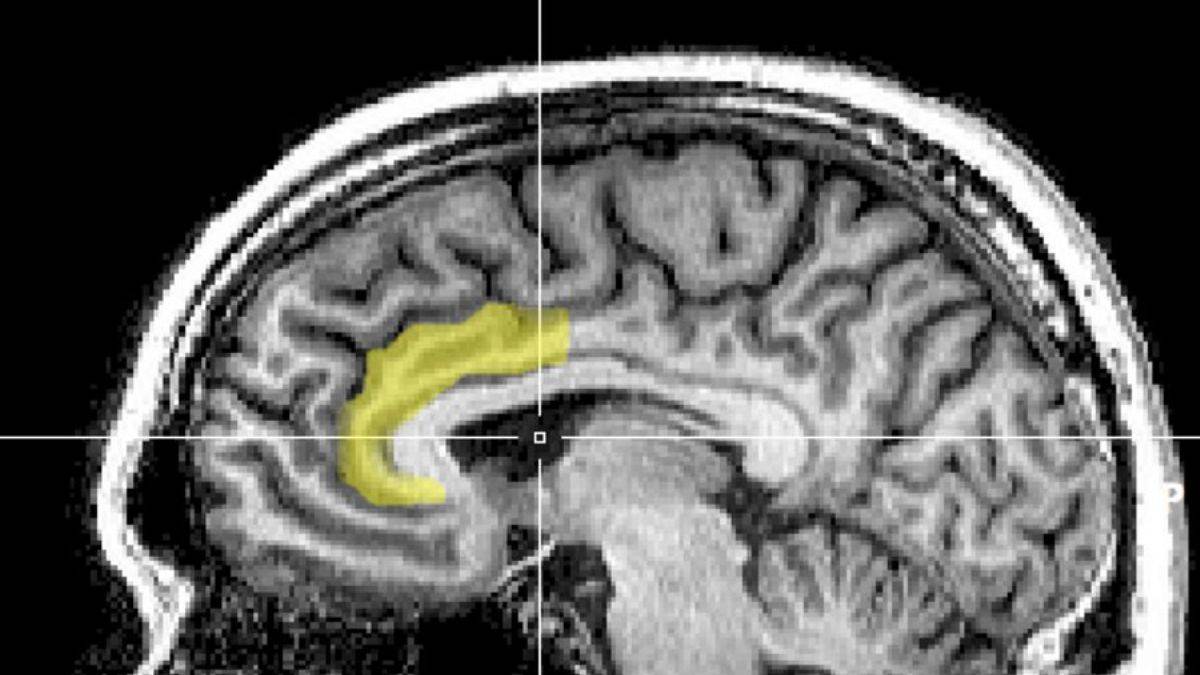

Gri maddede kayıp:

Gri madde; hareketi, hafızayı ve duyguları kontrol etmekten sorumludur. Bir araştırmaya göre, telefon bağımlısı birinin beyni uyuşturucu kullanıcılarının beynine benzer şekilde daha ince gri maddeye sahip (MRG).